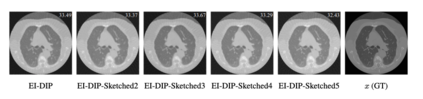

Equivariant Imaging (EI) regularization has become the de-facto technique for unsupervised training of deep imaging networks, without any need of ground-truth data. Observing that the EI-based unsupervised training paradigm currently has significant computational redundancy leading to inefficiency in high-dimensional applications, we propose a sketched EI regularization which leverages the randomized sketching techniques for acceleration. We then extend our sketched EI regularization to develop an accelerated deep internal learning framework -- Sketched Equivariant Deep Image Prior (Sk.EI-DIP), which can be efficiently applied for single-image and task-adapted reconstruction. Our numerical study on X-ray CT image reconstruction tasks demonstrate that our approach can achieve order-of-magnitude computational acceleration over standard EI-based counterpart in single-input setting, and network adaptation at test time.